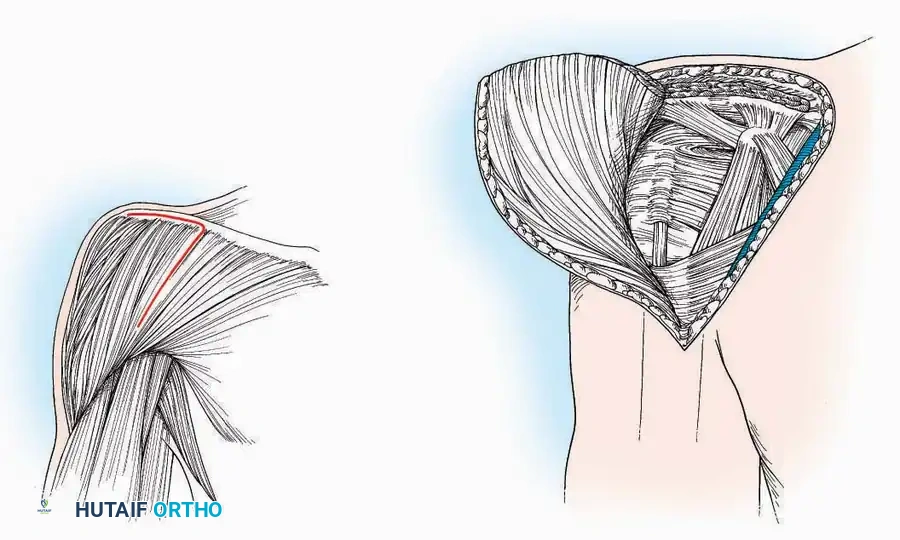

Lateral Approach (Extensile Lateral)

This is the workhorse approach for open reduction and internal fixation (ORIF) of displaced intra-articular calcaneal fractures.

Indications: ORIF of calcaneus fractures, lateral wall exostectomy, subtalar arthrodesis.

Positioning: Lateral decubitus with the operative leg up, or supine with a large bump under the ipsilateral hip to internally rotate the leg.

Surgical Technique:

* Incision: Begin the incision on the lateral margin of the Achilles tendon near its insertion. Extend it distally to a point 4 cm inferior and 2.5 cm anterior to the lateral malleolus. (For trauma, a classic L-shaped extensile incision is often used, dropping straight down anterior to the Achilles, then curving gently toward the base of the 5th metatarsal).

* Superficial Dissection: Divide the superficial and deep fasciae. It is imperative to create a "full-thickness" flap containing skin, subcutaneous fat, and periosteum to prevent flap necrosis.

* Nerve Protection: The sural nerve crosses the proximal and distal limbs of this approach. It must be identified and protected within the anterior flap.

* Deep Dissection: Isolate the peroneal tendons (longus and brevis). Incise and elevate the periosteum below the tendons to expose the lateral wall of the calcaneus.

* Tendon Management: If severe deformity or infection is present, the peroneal tendons may be divided via Z-plasty and repaired at the conclusion of the case, though this is rarely necessary in modern fracture care.